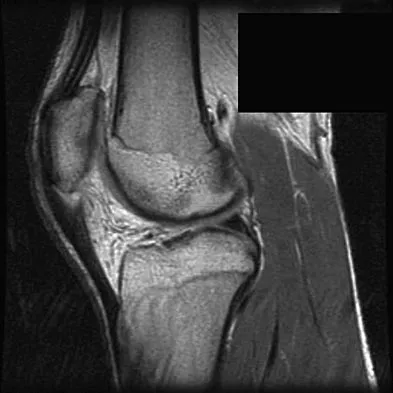

A 17-year-old basketball player and pole vaulter who has had anterior knee pain for the past 18 months now reports a recent inability to jump. Based on the MRI scan shown in Figure 11, management should consist of

Explanation